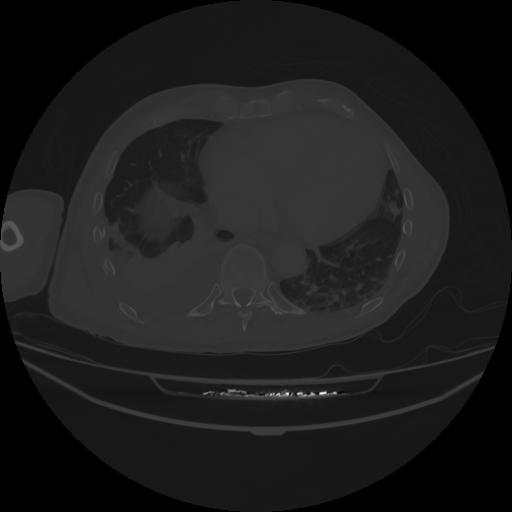

5 CUERPO,CE,Vol,1.0,CUERPO,,